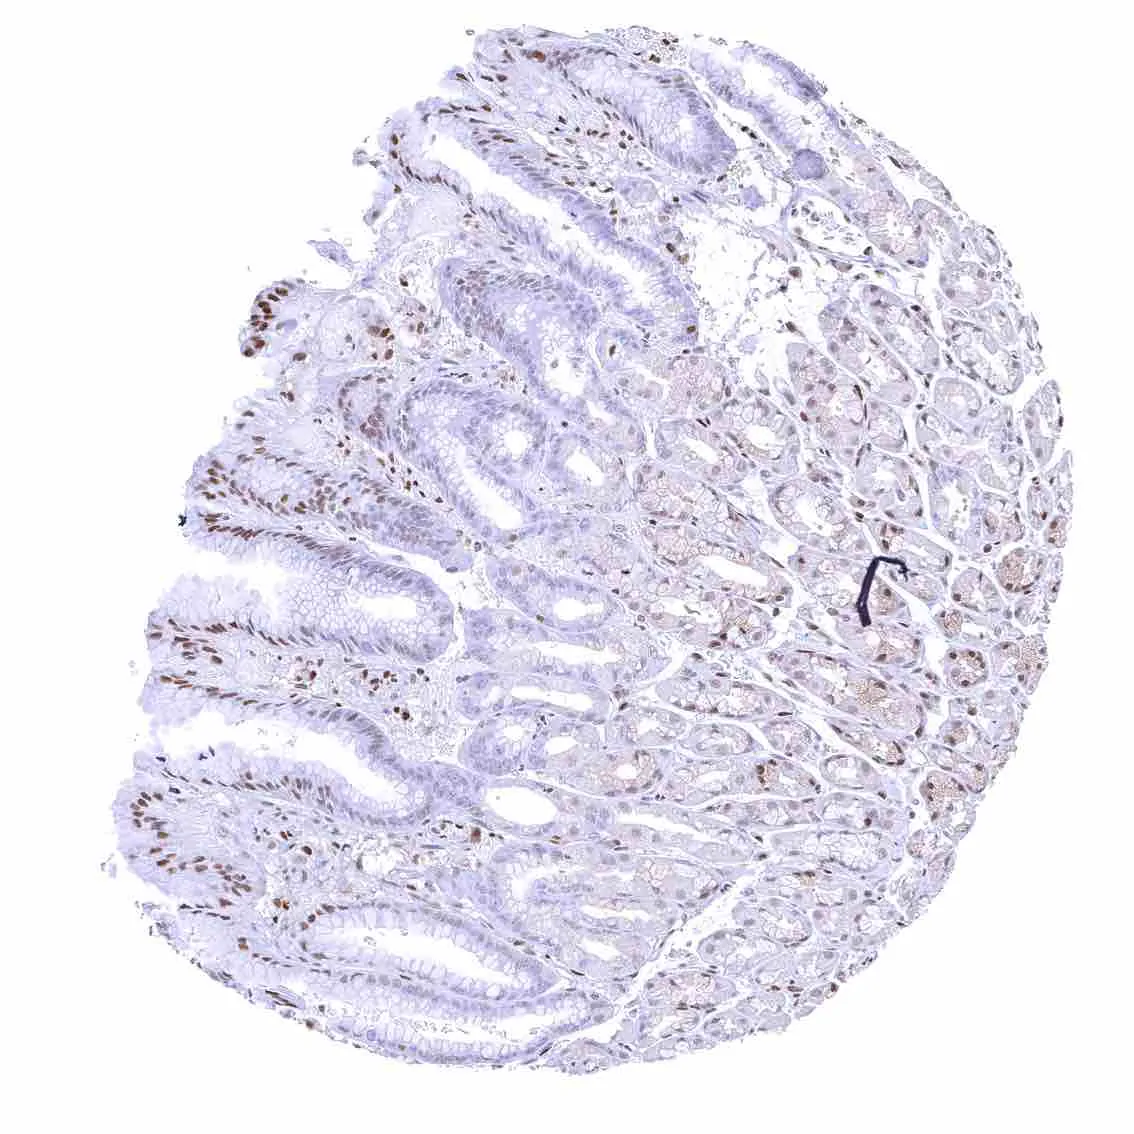

Appendix, mucosa – Among epithelial cells, nuclear p27 staining predominates in superficial epithelial cells. Most p27 staining occurs in lymphatic cells, however.